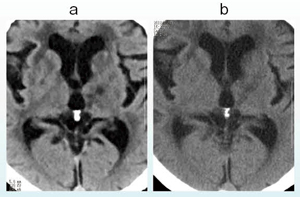

図5 症例3:CTPとMRP(ASL)の比較

a:CTP(Definition Flash)

b:ASL(MAGNETOM Skyra)

一般に,CTPはnon-diffuseだが,ASLはdiffusableとされる。ASLの撮影方法はメーカーによって異なり,シーメンス社の3T MRI「MAGNETOM Skyra」の場合はTⅠを変えながら撮ることで血流画像が変化する。SPECTとよく似た画像で,本症例では血流が保たれていることがわかる(図5)。